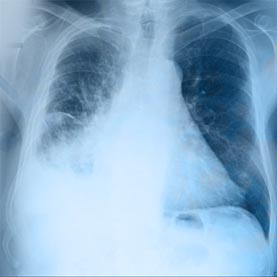

▪ Chest X-ray